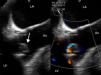

Three days after discharge she was readmitted with fever and dyspnea, along with elevated CRP and anemia. Blood cultures were positive for C. albicans. Antifungal therapy with liposomal amphotericin B was initiated but subsequent blood cultures remained positive. A transesophageal echocardiogram (TEE) demonstrated large vegetations on the aortic valve and a periprosthetic leak resulting in mild aortic regurgitation, establishing the diagnosis of FE (Figure 1).